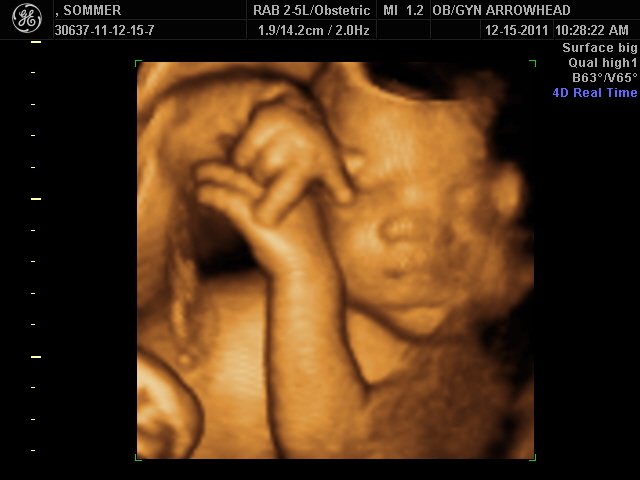

We offer complimentary 3D/4D Ultrasounds to all our OB patients around 30 weeks! The following photos are some examples of our work, shown with permission from our patients.